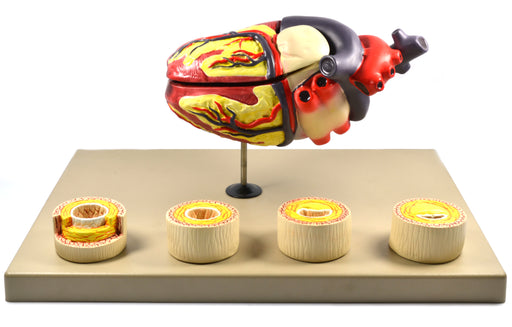

Eisco Labs Model of Human Heart Conditions Pathology; Larger than life size (10"); Artery Cross sections 2.5" in diameter

Heart on stand - larger than life size (approx. 10") Four artery cross sections (2.5" in diameter) showing the progression of atherosclerosis Vivi...

View full detailsAM0280 -